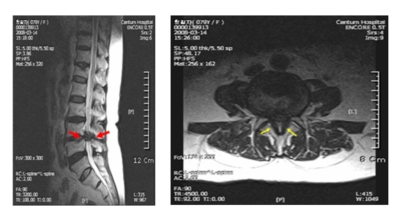

요추관 협착증은 척추 내 신경이 지나가는 통로가 좁아지는 현상으로 기인해서 신경이 눌리면서 이에 따른 여러가지 증상을 유발하는 질환을 의미해요.

허리 협착증은 척추관이 좁아지게 되면서 신경을 압박하게 되어 허리통증과 또한 다리에도 여러가지 증상을 일으키게 되는데, 발생 원인은 주로 노화로 인한 퇴행성 변화가 많았지만 요즈음는 옳지 않은 자세로 오랫동안 앉아있는 사람들이 많아지면서 생기는 경우도 많아졌으며, 선천적인 요인으로 나타나는 경우도 있답니다.